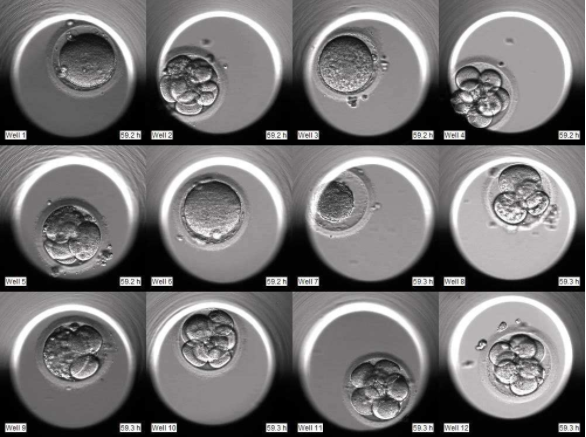

(2)持续记录:系统内的显微镜会按照预设的时间间隔(例如每分钟)自动对胚胎进行拍照。成千上万张静态照片被系统软件整合起来,形成一段完整记录胚胎从受精到囊胚整个发育过程的动态延时视频。

(1)细胞分裂的同步性:第一次分裂、第二次分裂的时间点是否精准?分裂过程是否整齐有序?

(2)异常分裂现象:是否存在直接分裂(如从1细胞直接分裂为3细胞)、细胞质碎片出现的时机和多少、有无出现多核等动态异常?这些在传统静态观察中可能被忽略的细节,在视频中清晰可见。

(3)关键事件的时间点:研究表明,某些发育事件发生的时间点(如原核消失时间、细胞分裂间隔等)与胚胎的染色体正常率(非整倍体率)存在一定的相关性。

通过分析这些动态形态学参数,胚胎学家可以构建更复杂的评估模型,对胚胎进行更为细致的筛选和排名。这意味着,选择标准从单一的“颜值”(静态形态)部分延伸到了“成长轨迹”(动态行为),为胚胎学家提供了更全面的决策参考。